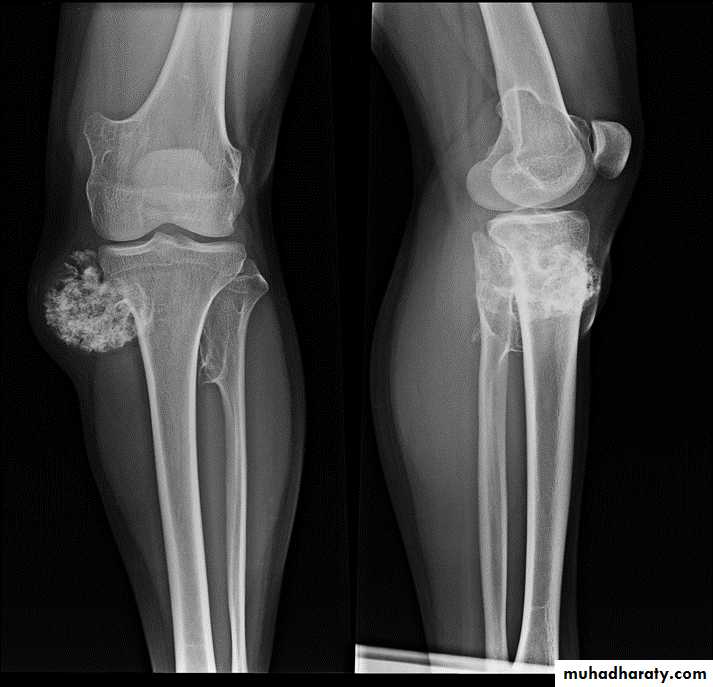

* Multiple osteochondromas are seen in Diaphyseal aclasia.

Osteochondroma of the distal femur.

The cortex is continuous with that of the underlying bone and trabecular bone merges with that of the femur. A well-defined cartilage cap contains calcification and is directedaway from the joint.

Diaphyseal aclasia.

Multiple osteochondromasEnchondroma :